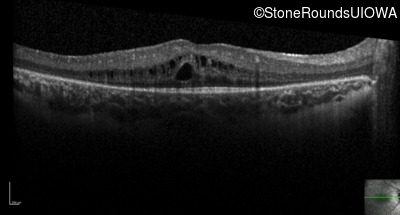

Optical Coherence Tomography - Right - 20/25 -2

Exemplar / OCT Stack

Optical Coherence Tomography - Left - 20/32